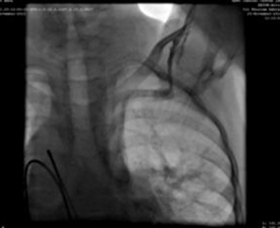

Foi utilizada uma bainha de parto 9F, que foi avançada e colocada na aorta descendente sobre o fio-guia super-rígido. Uma MemoPartTM cone shape PDA occluder 14/12 mm, was attached to the delivery cable and progressed across the delivery sheath. The placement of the occlude was proper with no residual flow.

Resultados

Sucesso cirúrgico, sem complicações intraoperatórias graves, ecocardiografia 24h após a oclusão mostra boa colocação, sem shunt residual no defeito.